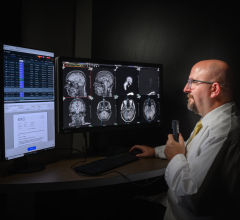

The NovaMG breast imaging viewer combines the tool set of NovaPACS with customizable mammographic reading and hanging protocol sequences. FDA 510(k) cleared and IHE compliant, it supports multi-modality viewing and iCad and R2 structured reports.

The viewer enables direct receipt of digital mammographic images from the modality while pre-fetching from the PACS archive is initiated via DICOM modality worklist.

Offered as an option to NovaRad’s existing radiologist view stations, the viewer provides all pixels viewing that allows for searching of all image pixels and incorporates Tabár’s systematic viewing masks to enhance perception of subtle radiographic abnormalities. All annotations and additions to image information such as Grayscale Softcopy Presentation State (GSPS), queried and retrieved images and structured reports are stored in the PACS upon completion of interpretation.

NovaMG automatically populates the diagnostic findings to a mammography reporting system and facilitates work list synchronization for recall-report exporting from either the RIS or mammography reporting system.

In addition to NovaMG, NovaRad offers NovaPACS, NovaRIS, NovaPro for radiologist groups, NovaCardio PACS, and ClinicPACS orthopedic PACS radiology technologies. Its systems are used by more than 450 facilities around the globe.